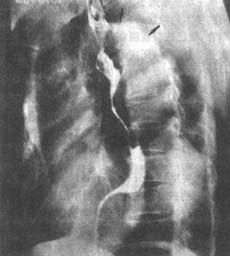

胸主动脉瘤的发现除根据症状和体征外X线检查有帮助在后前位及侧位片上可以发现主动脉影扩大从阴影可以估计病变的大小位置和形态在透视下可以见到动脉瘤的膨胀性搏动但在动脉瘤中有血栓形成时搏动可以不明显主动脉瘤须与附着于主动脉上的实质性肿块区别后者引起传导性搏动主动脉造影可以作出鉴别(图12)超声心动图检查可以发现升主动脉的主动脉瘤病变处主动脉扩大X线计算机断层扫描(CT)对诊断也有用

图1 胸主动脉瘤的后前位X线片

示升主动脉边缘较膨隆主动脉增宽食管主动脉压迹增宽降主动脉轮廓显著不整齐有多发动脉瘤形成

图2 胸主动脉瘤的左前斜位X线片

示主动脉弓部上缘可见波浪状轮廓(↑)食管随主动脉迂曲波浪状边缘代表相邻主动脉的不规则扩张和动脉瘤